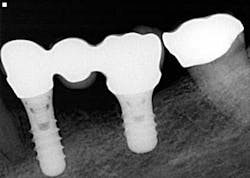

What would it be like if we could replace every missing tooth with an implant? The possibilities for implants and their implication in the future of dentistry are endless, and yet not all people are candidates or are able to do implants (financially, medically, etc.). We have to acknowledge these circumstances that dictate us to consider and offer alternative replacement means to these patients, mainly dentures and partial dentures.

The use of adhesives and inherent hassle of dentures and partials will often give rise to the incentive to look into more permanent options. Again (assuming medical history is not an issue), review implant alternatives and how patients can improve the status quo — bridges, All-On-4, implant-supported dentures, fixed hybrid prostheses, etc.